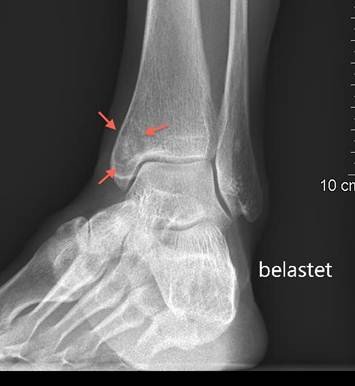

Knochenzyste Innenknöchel

Bei stetiger Schmerzzunahme wurde im Januar 2012 eine Magnetresonanztomographie (MRI) des Sprunggelenkes angefertigt, welche eine Zyste von 1.3 cm Breite, 1.9 cm Höhe und 1.4 cm Tiefe im Innenknöchel zutage förderte. Die Zyste, welche einem Hohlraum im Knochen entspricht, hatte an der Innenseite des Knöchels eine Verbindung zum oberen Sprunggelenk. Diese Verbindung war Grund dafür, dass die Zyste mit eingedickter Gelenkflüssigkeit gefüllt war – der Druck der Flüssigkeit wiederum erklärte die Schmerzen sowie die Grössenzunahme der Zyste.

Im Laufe Zeit kam es zu einer zunehmenden Erholung. Eine vollständige Schmerzfreiheit stellte sich ca. fünf Monate nach der Operation ein – die Patienten war bei der letzten Kontrolle Anfang September 2012 bereits einige Wochen voll sportfähig, auch Joggen war problemlos möglich. Die an diesem Tag angefertigten Röntgenaufnahmen des oberen Sprunggelenkes zeigten unauffällige Verhältnisse – d. h. die Zyste war nur noch in ihren ehemaligen Umrissen erkennbar. Bei völliger Zufriedenheit der Patientin und auch objektiv sehr gutem Verlauf konnte die Behandlung abgeschlossen werden.